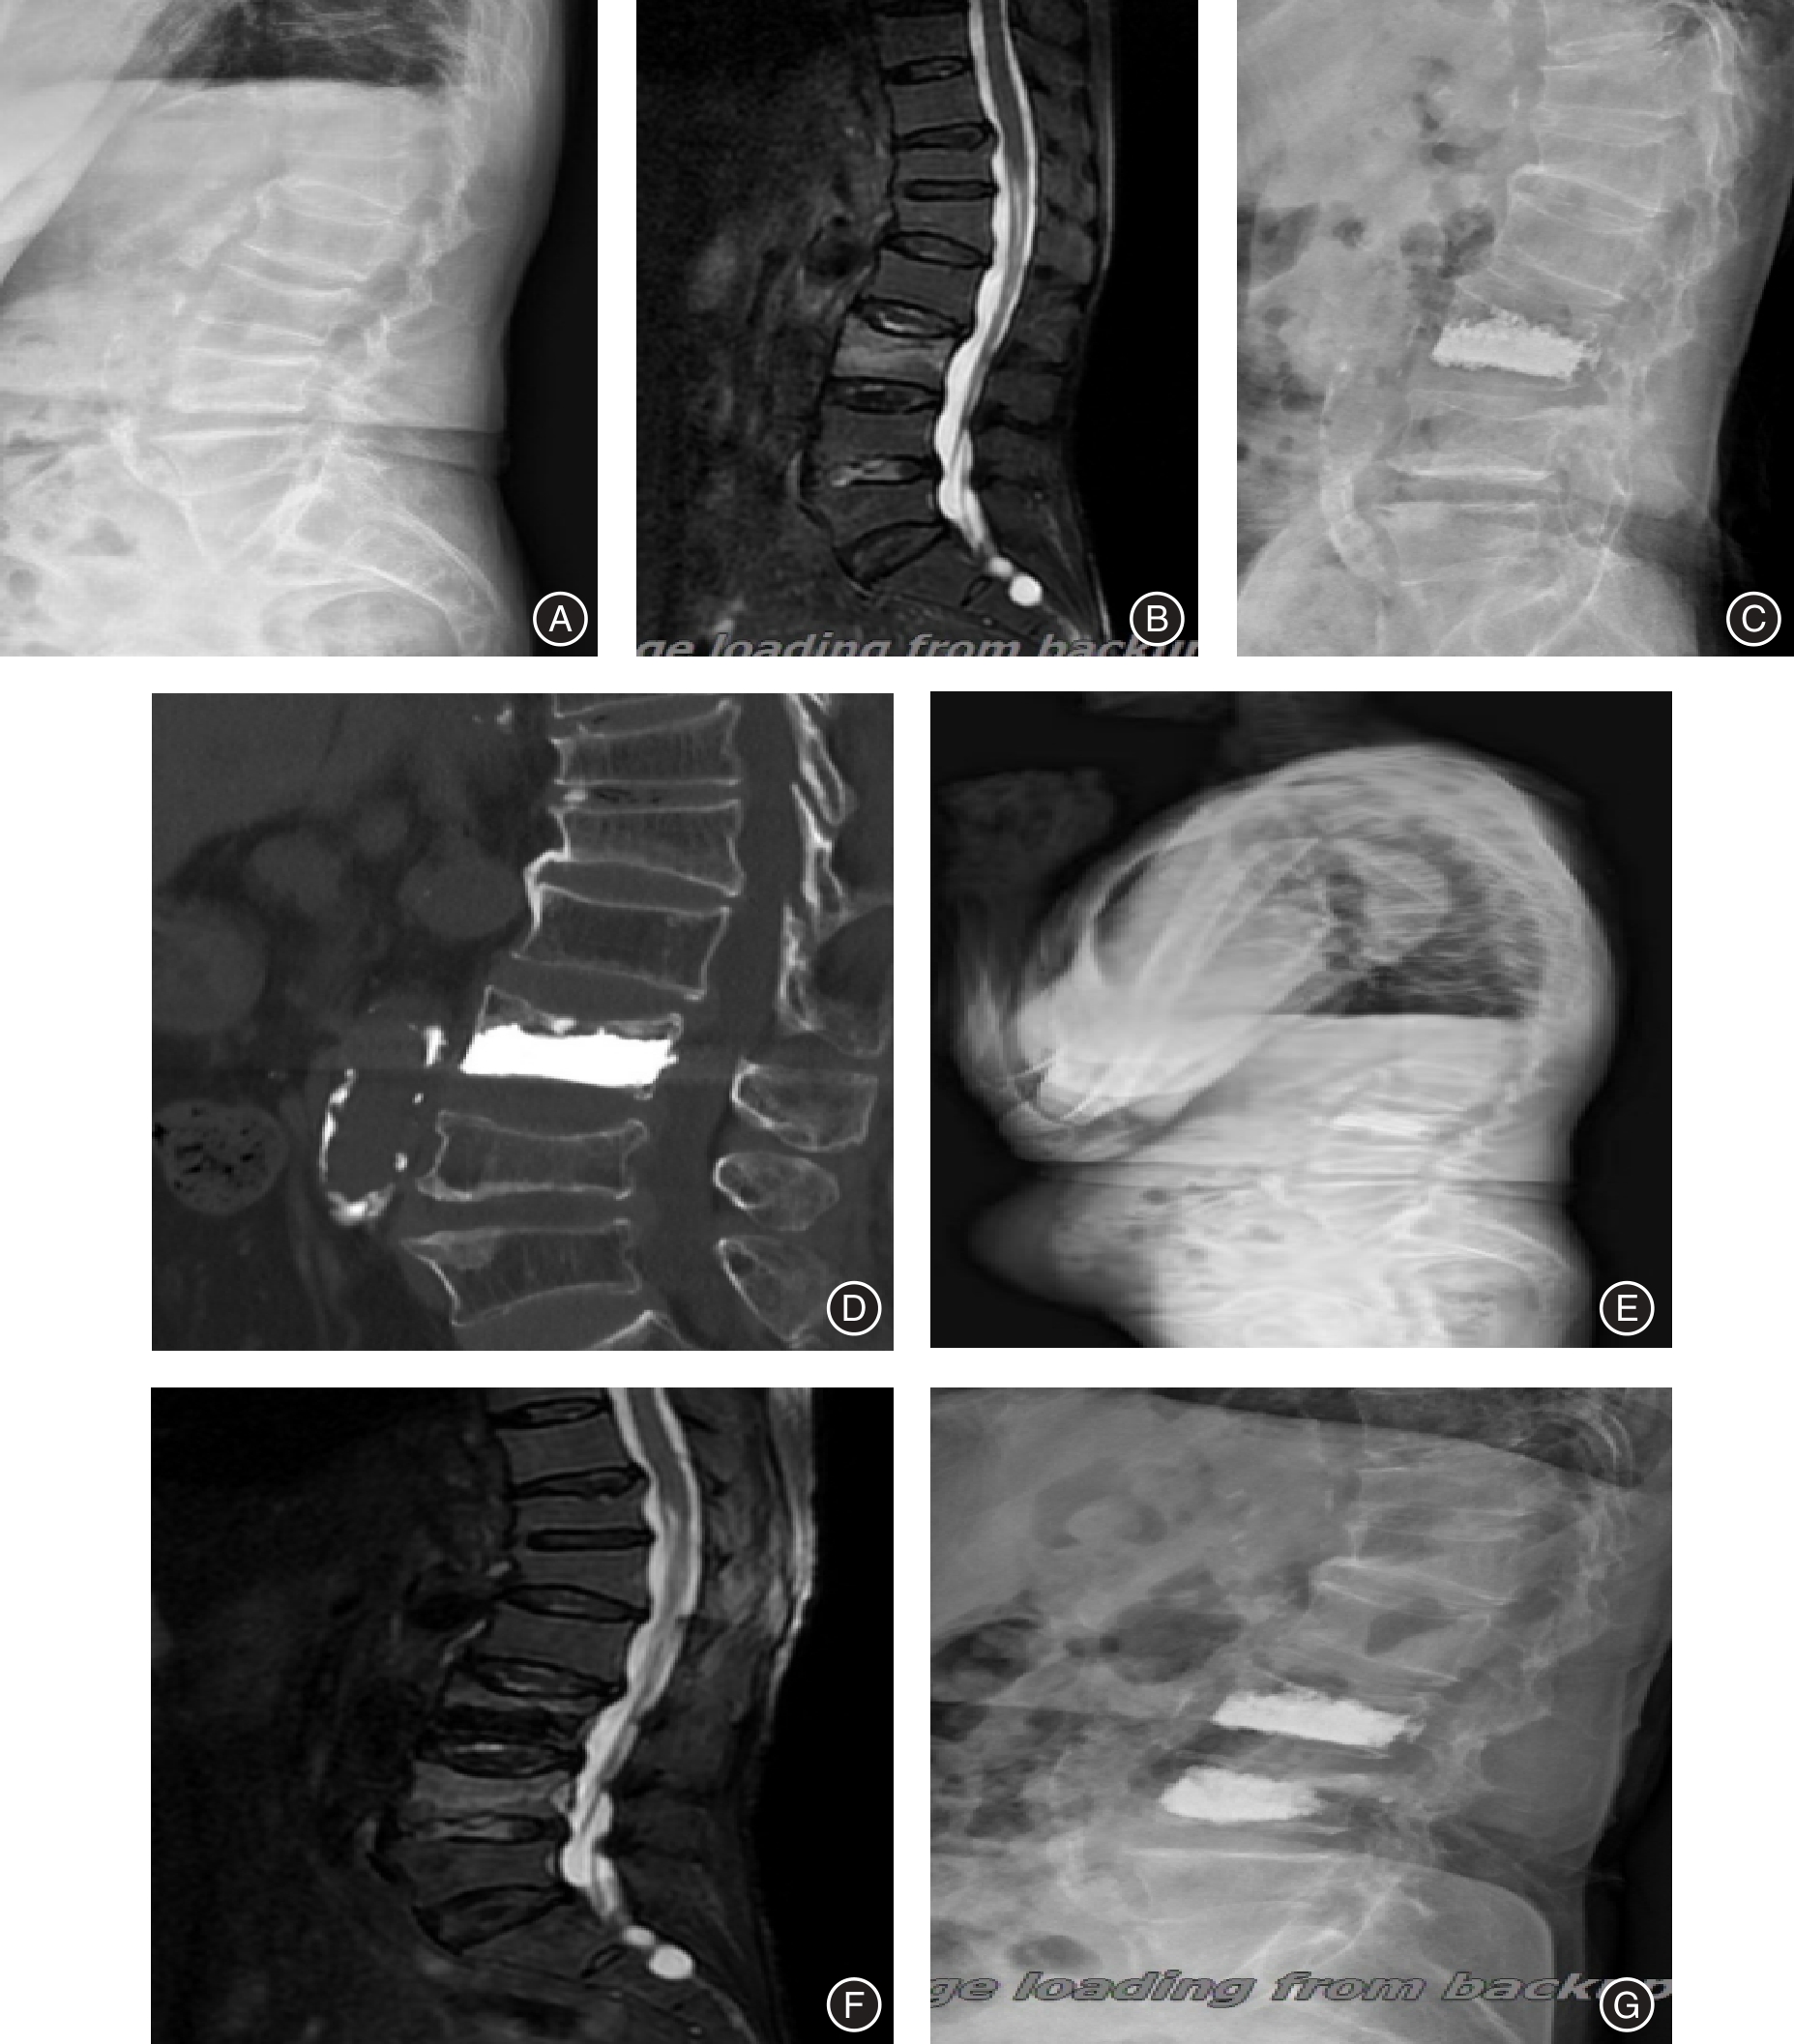

Objective To analyze the influencing factors for adjacent vertebral compression fractures (AVCF) after percutaneous kyphoplasty (PKP) in patients with osteoporotic vertebral compression fractures (OVCF), taking into account the sagittal parameters of the spine-pelvis, fracture characteristics, and treatment-related clinical features. Methods The research subjects were selected from OVCF patients admitted to the hospital between November 2020 and August 2023. A total of 240 cases were included, and their clinical data were retrospectively analyzed. All the patients underwent PKP surgery and were followed up for 2 years. Based on whether the selected patients experienced AVCF during the follow-up period, they were divided into the occurrence group (54 cases) and the non-occurrence group (186 cases). The clinical data and spinal pelvic sagittal plane parameters of the two groups were compared, and the risk factors were analyzed by multivariate Logistic regression analysis. The predictive value of the regression equation was analyzed by receiver operating characteristic (ROC) curves. Results The proportions of patients with diabetes, Ⅱ/Ⅲ degree fracture compression, initial fracture site T10-L2, bone cement intervertebral disc leakage, multi-segment fracture, and intervertebral disc injury in the occurrence group were 53.70%, 62.96%, 72.22%, 40.74%, 44.44%, and 33.33%, respectively, which were higher than those of 24.19%, 47.31%, 45.70%, 13.44%, 19.35%, and 13.98% in the non-occurrence group. The recovery rate of vertebral body height was lower than that in the non-occurrence group, and the TK, SVA, and TPA were higher than those in the non-occurrence group (P < 0.05). Diabetes (OR = 2.408), Ⅱ/Ⅲ degree fracture compression (OR = 2.838), bone cement disc leakage (OR = 1.547), multi-level fracture (OR = 2.155), disc injury (OR = 3.043), elevated TK (OR = 2.081), elevated SVA (OR = 2.298), and elevated TPA (OR = 1.636) were independent risk factors for AVCF in OVCF patients after PKP (P < 0.05). The increased vertebral height recovery rate (OR = 0.328) was an independent protective factor (P < 0.05). A regression equation was constructed: logit (P) = -7.087 + diabetes × 0.879 + fracture compression degree × 1.043 + bone cement intervertebral disc leakage × 0.436 + multi-level fracture × 0.768 + intervertebral disc injury × 1.113 - vertebral height recovery rate × 1.114 + TK × 0.733 + SVA × 0.832 + TPA × 0.436. The construction of the Logistic multiple regression diagnostic regression equation is effective. The ROC curve shows that when logit (P) > 0.174, the area under the curve (AUC) value is 0.898, and the diagnostic sensitivity and specificity are 83.33% and 82.80%, respectively. Conclusions Diabetes, Ⅱ/Ⅲ degree fracture compression, bone cement disc leakage, multi-level fracture, disc injury, elevated TK, elevated SVA, and elevated TPA were identified as independent risk factors for AVCF in OVCF patients after PKP, the increased vertebral height recovery rate was an independent protective factor. The regression equation constructed exhibited a high predictive value.